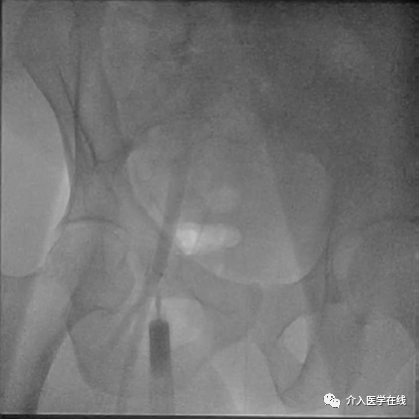

熟悉股动脉的解剖结构对于创建安全的血管通路和预防并发症极其重要。CFA 是髂外动脉的延续,在腹股沟韧带下方分叉为股浅动脉 (SFA) 和股深动脉 (PF)。在大多数病例 (77%) 中,分叉位于股骨头水平以下。图 1 显示 CFA 的走行和分支及对应的骨性标志。

图 1:血管造影走行及股动脉分支 (1) 腹壁下动脉;(2) 旋髂深动脉;(3) 股总动脉;(4) 股深动脉;(5)股浅动脉